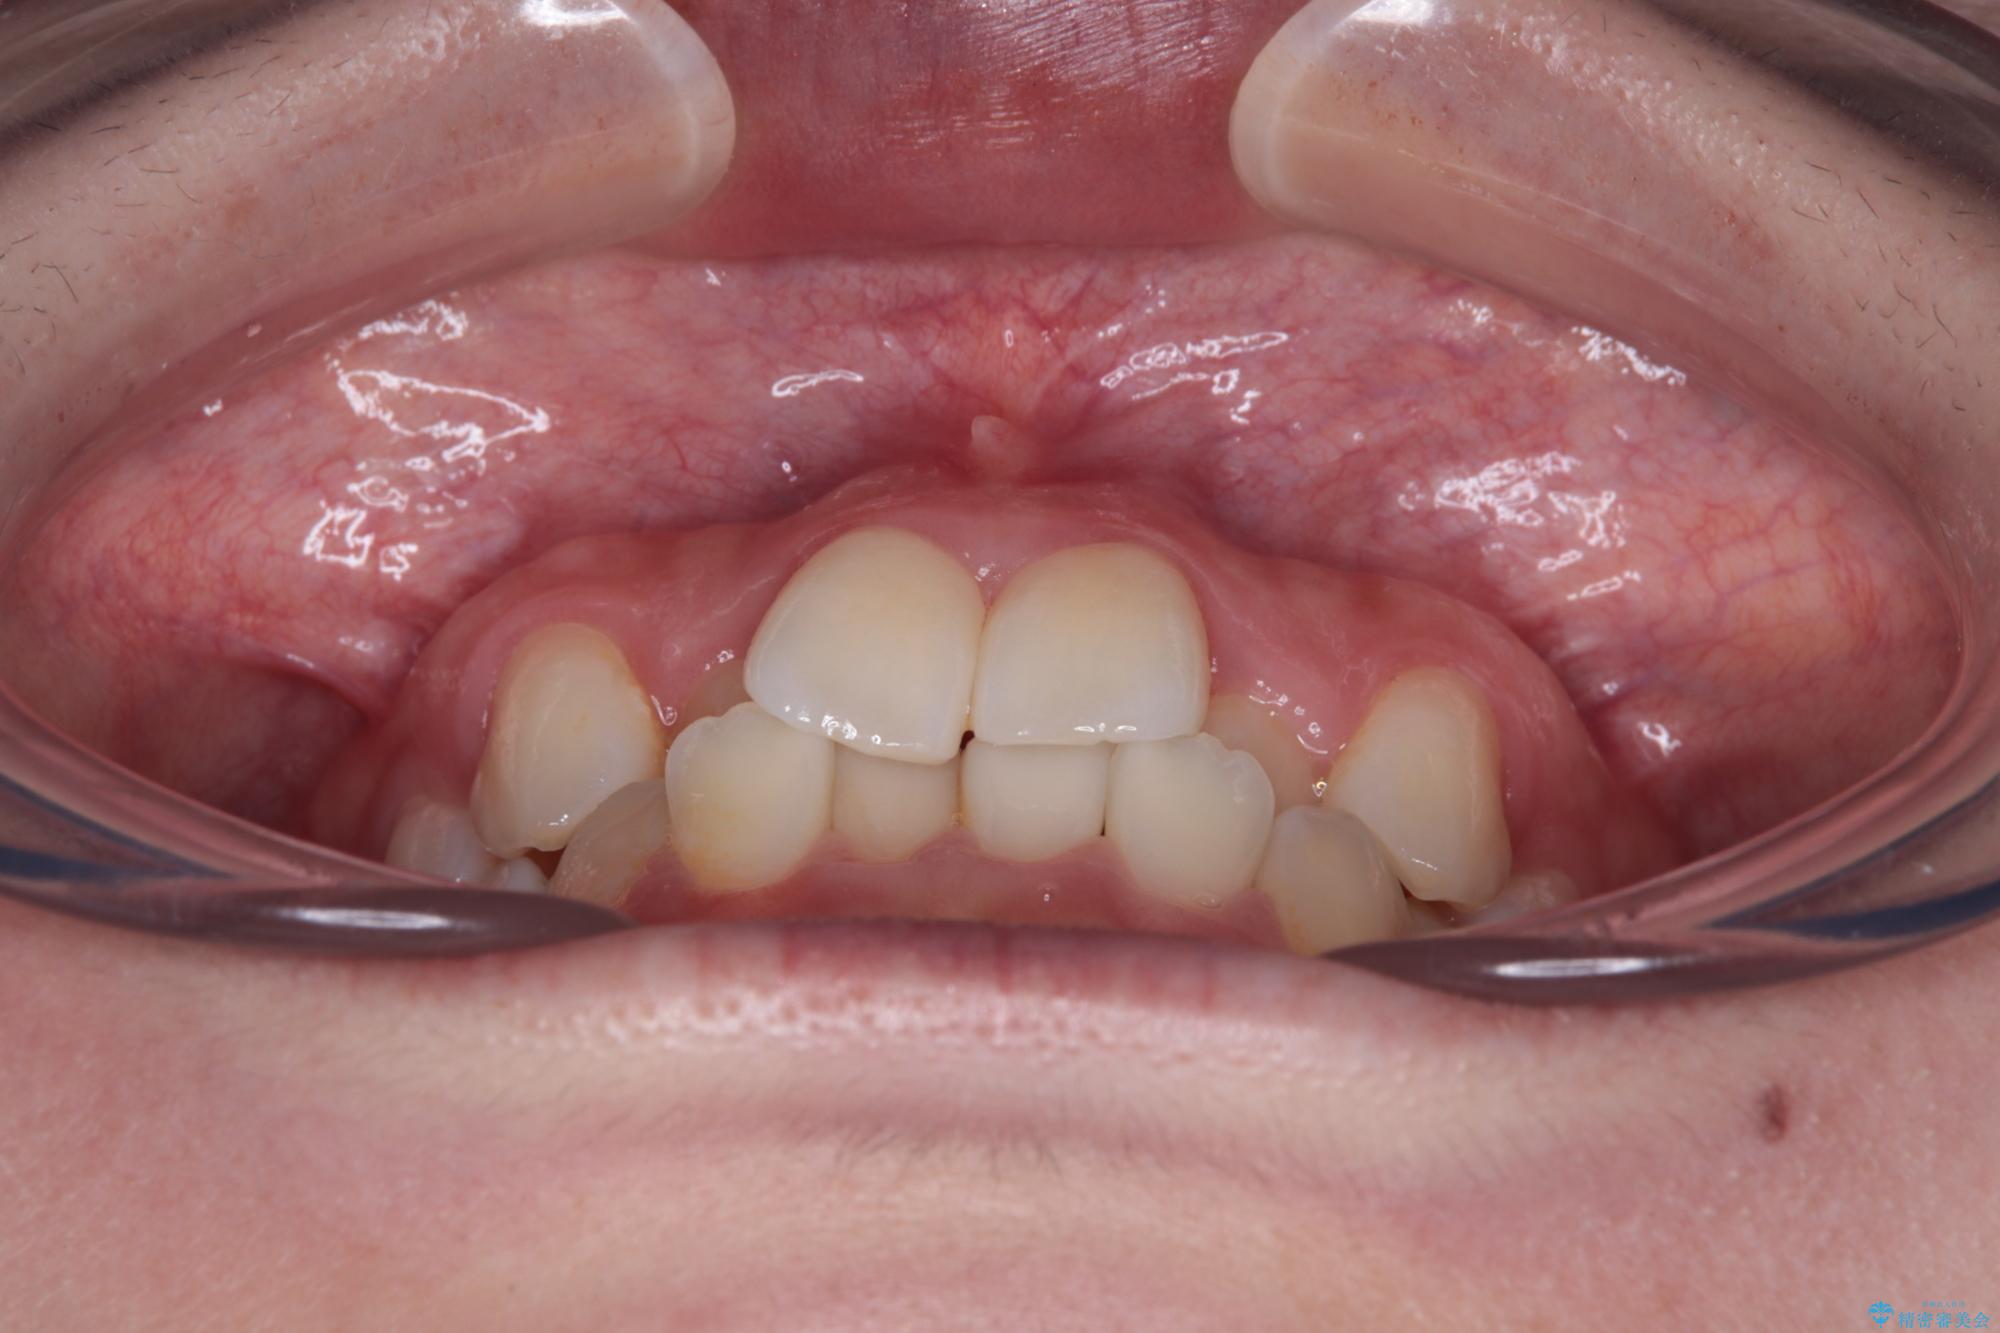

- 上顎前歯のクロスバイトを気にして来院された患者様です。

ワイヤー矯正でもマウスピース矯正でも対応可能でしたが、マウスピースによる自己管理に一切の自信がないとのことで、ワイヤー装置にて矯正治療を行うこととしました。

装置の外見を気にしていましたが、短期間で治療を終えることができるだろうと伝えると、安価であるメタルブラケットを選択されました。

想定通り、1年強で綺麗に仕上げることができました。